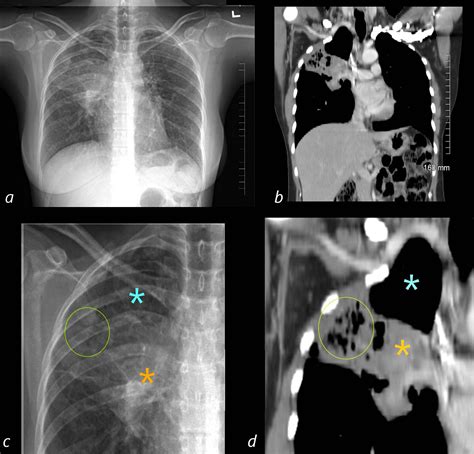

• Chest X-ray: An initial imaging test to detect any abnormalities in the lungs.

• CT Scan: A more detailed imaging test that provides a clearer picture of the lung tissue and any potential tumors.